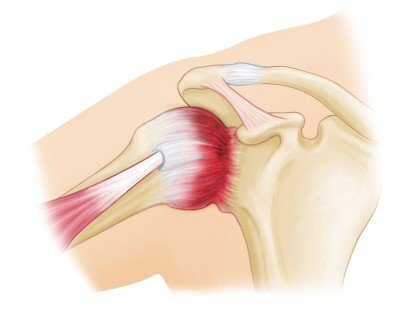

Frozen shoulder, clinically termed adhesive capsulitis, is a highly restrictive pathology targeting the connective tissue envelope of the joint.

The condition occurs when the shoulder joint capsule becomes profoundly inflamed, thickened, and contracted. This global capsular tightening severely restricts both active movement (you moving your arm) and passive movement (someone else moving your arm).

Unlike most subacromial or rotator cuff conditions where passive motion remains intact, frozen shoulder uniquely limits movement in all operational planes with a distinct, characteristic ‘hard stop’ mechanical block upon clinical testing.